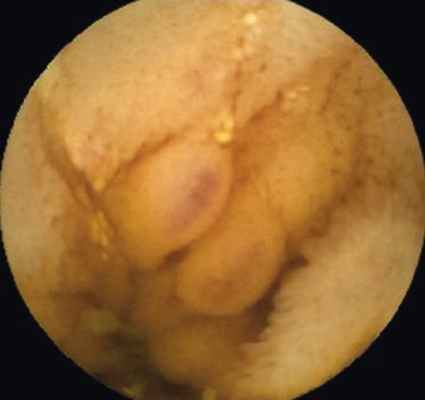

Пациентка В . , 19 лет, с подтвержденным диагнозом «болезнь Крона (язвенно-геморрагический энтерит)» с 2012 г. неоднократно находилась на обследовании и лечении в отделении воспалительных заболеваний кишечника Московского клинического научно-практического центра. Длительное время получала месалазин, азатиоприн, инфликсимаб; неэффективность проведенного лечения послужила поводом для назначения биологической терапии (адалимумаб). Однако стойкой ремиссии добиться не удавалось. При очередном обследовании в марте 2015 г. пациентке была выполнена колоноскопия, во время которой выявили незначительные воспалительные изменения ободочной кишки и терминального отдела подвздошной кишки: афтозный колит, афтозный терминальный илеит. Данные, полученные при традиционной эндоскопии, не соответствовали клиническому состоянию больной. Для оценки распространенности и степени поражения кишечника ей была назначена КЭ. В результате видеокапсульного исследования определено поражение глубоких отделов тонкой кишки на значительном протяжении в виде множественных язв и отека складок, а также обнаружено сужение просвета тонкой кишки ( рис. 1-4 ).

Рис. 2. Отек слизистой оболочки, псевдополипы с эрозиями, сужение просвета тонкой кишки. Фото авторов